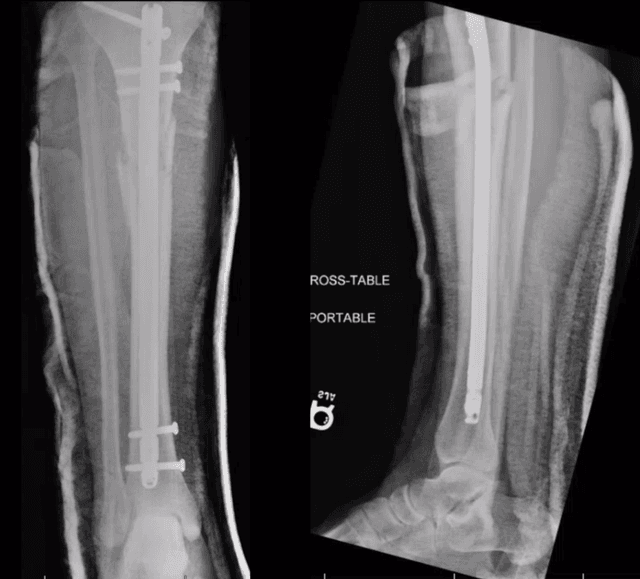

Pre-op

Post-op